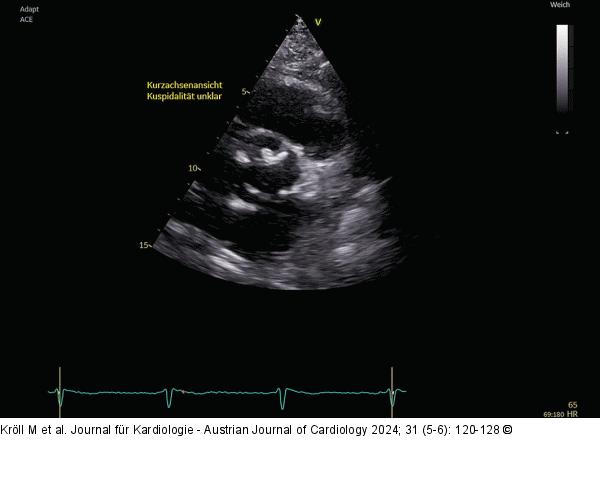

Abbildung 1: Echo 2D-TTE, Kurzachsenansicht, Kuspidalität unklar |